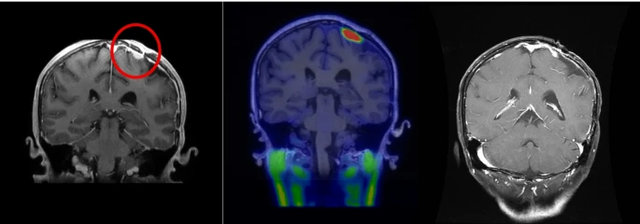

研究共纳入13例患者,所有患者都接受了一次BNCT。9名非颅底脑膜瘤患者中有5名患者(56%)对BNCT有反应,而颅底组则没有。中位无进展生存期(PFS)分别为18.56个月和15.84个月。一名复发性凸性非典型脑膜瘤患者经BNCT治疗两个月后肿瘤明显缩小。